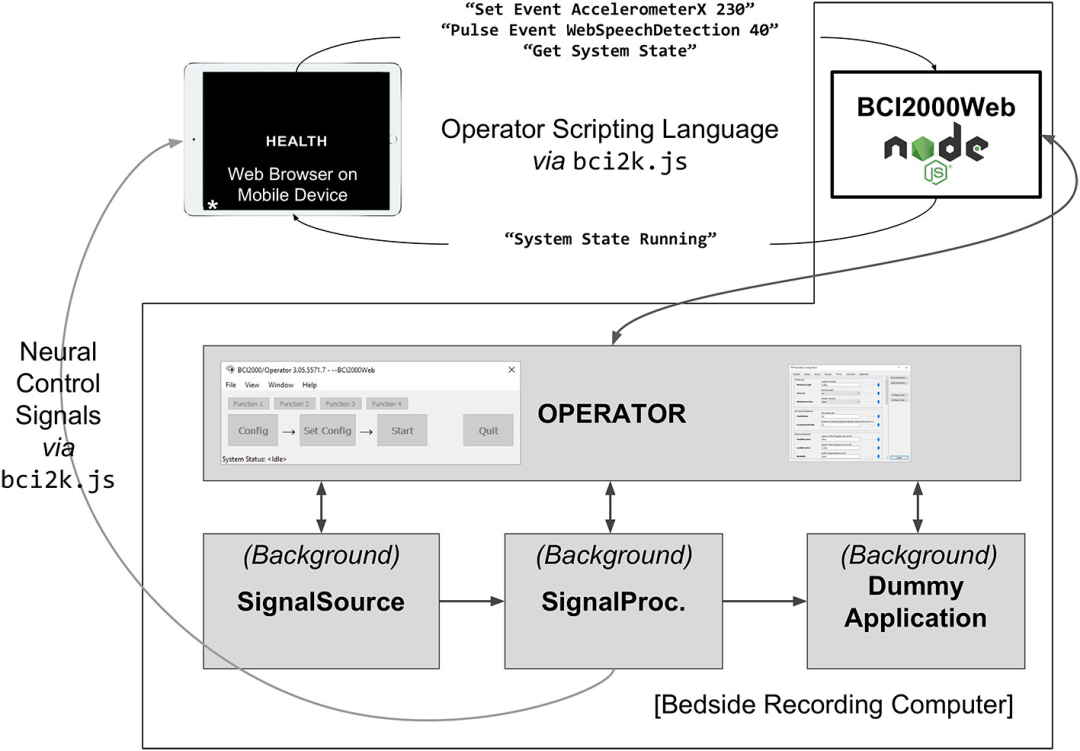

本文开发了一个名为BCI2000Web的服务器和过滤器模块,可以实现浏览器和BCI2000发行版之间的实时直接通信,促进许多新颖的应用程序。 本文还提出了一个JavaScript模块bci2k.js,允许Web开发人员以易于使用和直观的方式使用此界面创建范式和可视化。

D3.js可以将我们的数据可视化,甚至使用WebAudio API进行超声化,可以帮助我们实时理解数据。现有的BCI软件套件通常提供一定数量的进程间通信,通常通过用户数据报协议user datagram protocol (UDP)或共享内存公开。然而,出于安全考虑,浏览器通常不允许Web应用程序原生访问UDP;此外,BCI2000的AppConnector接口等现有通信方案不能很好地扩展到高数据量。BCI2000现有的进程间通信工具在设计时考虑到了控制信号的传输,为了简单起见,使用ASCII而不是二进制来通信信号,代价是将数据速率膨胀到8倍-这种方法是成功的,直到需要传输原始和处理过的ECoG数据流。现代浏览器实现了一种建立在TCP之上的协议,称为WebSocket (Fette, 2011),它允许HTTP客户端将现有连接升级为通用的实时双向二进制/ASCII通信接口。WebSockets非常适合于将原始大脑信号、提取的神经特征和处理的控制信号从BCI软件套件传输到支持浏览器的设备上的web应用程序,以及将辅助传感器信息从web应用程序传输回本机软件套件,所有这些都是实时的。在本文中,我们将上述接口的实现作为BCI2000的插件,我们称之为BCI2000Web。

BCI2000环境是一个通用计算框架,通常用于构建BCI,基于四个二进制可执行文件:信号源模块,从受支持的放大器获取生理数据;信号处理模块,提取神经特征并将这些特征转换为控制信号;应用程序模块,对这些控制信号做出反应并向主体提供反馈;以及运算符模块,负责协调系统所有三个功能子模块的行为。信号从源模块传播到处理模块到应用程序模块,通过基于网络的协议(在旧版本的BCI2000中)或共享内存接口(在最近的迭代中)促进互联。每个模块都由一系列信号“过滤器”组成,这些过滤器接受传入的信号(作为逐个通道数组),并输出一个具有不同维度的派生信号。内置的运算符脚本语言允许在实验会话中自动设置和配置过滤器,操作员模块中存在Telnet接口,能够从BCI2000外部接受运算符脚本语言的文本命令。

笔者认为,仔细阅读这篇论文之后,其实不难想象出一种系统架构,其中用户的神经数据被发送到与服务器后端实时通信的浏览器应用程序,允许基于云的服务应用复杂的机器学习技术进行分析处理,更进一步,人们可以开发一个基于浏览器的应用程序,将多个用户的神经数据传输给彼此的客户,从而促进基于大脑的通信。由于专注于前端用户交互,许多软件包都是用JavaScript编写的,这些软件包支持交互式应用程序和可视化的快速实现。公共JavaScript API允许丰富的BCI交互,实验范式可以利用谷歌图像搜索等网络资源,在运行时提供各种量身定制的刺激。跨设备兼容性是将浏览器用作可视化和刺激演示平台的另一个优势。任何支持浏览器的设备(智能手机、平板电脑、PC甚至游戏机)都可以用于呈现刺激或可视化输出。由于这种“写完代码就能运行”的开发过程,临床医生可以使用WebFM从患者房间外的智能手机上实时查看映射结果,而ECoG功能映射由技术人员运行。